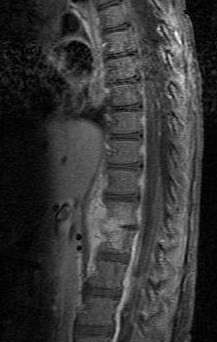

| Discitis in a 2 year old child. | |

Diagnosis is usually apparent on MRI although plain X-rays and CT examinations can be suggestive. The MRI will reveal air changes in the disc and possibly even external involvement involving the bone or epidural regions. A biopsy may be performed and helps with diagnosis in some cases but often an organism is not obtained. C-reactive protein levels and ESR levels will be elevated and are useful for treatment. Often, the white blood cell count will be normal and the patient will be afebrile.